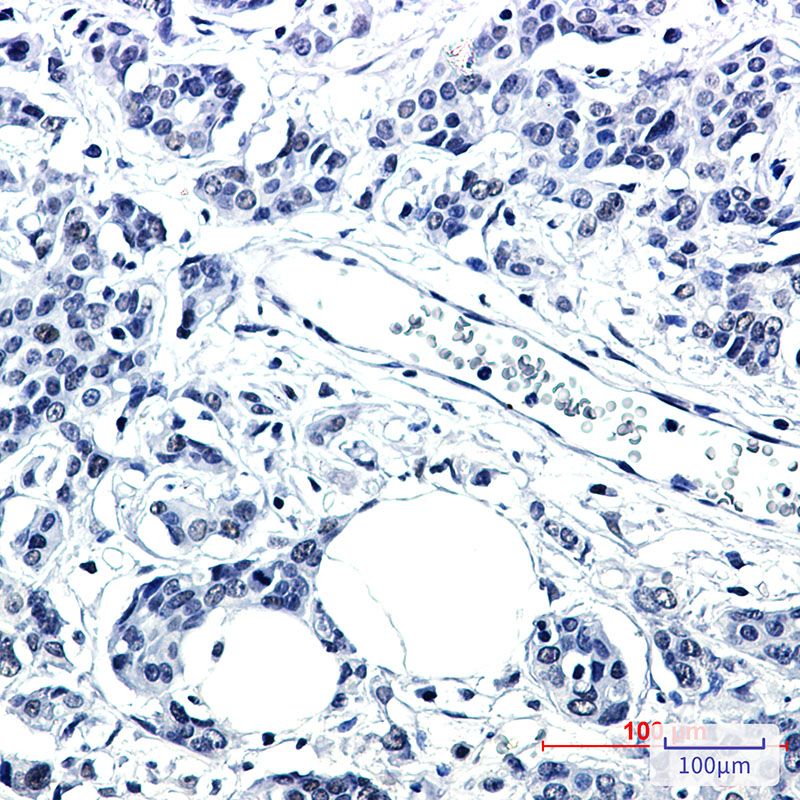

IHC 1/50-1/100 Human,Mouse,Rat

PNKP antibodies are essential tools in biomedical research, used to study the enzyme’s expression, localization, and interactions within DNA repair complexes. They facilitate applications like Western blotting, immunofluorescence, and immunohistochemistry, aiding in the exploration of PNKP’s mechanistic roles in cellular responses to DNA damage. Researchers also employ these antibodies to investigate PNKP’s involvement in cancer biology, particularly in contexts where DNA repair pathways are targeted therapeutically (e.g., PARP inhibitors, radiation therapy). Additionally, PNKP antibodies contribute to understanding neurodevelopmental defects linked to PNKP deficiencies, offering insights into potential therapeutic strategies. Their utility underscores the enzyme’s centrality in maintaining genomic integrity and cellular homeostasis.